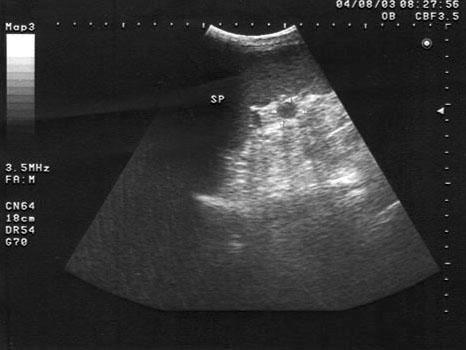

男、30岁,体检时发现脾门处光团,根据超声声像图诊断为?(?)A.副脾B.淋巴结C.转移癌D.脾脓肿E.左肾上腺肿瘤

问题 男、30岁,体检时发现脾门处光团,根据超声声像图诊断为?(?)

选项 A.副脾 B.淋巴结 C.转移癌 D.脾脓肿 E.左肾上腺肿瘤

答案 A